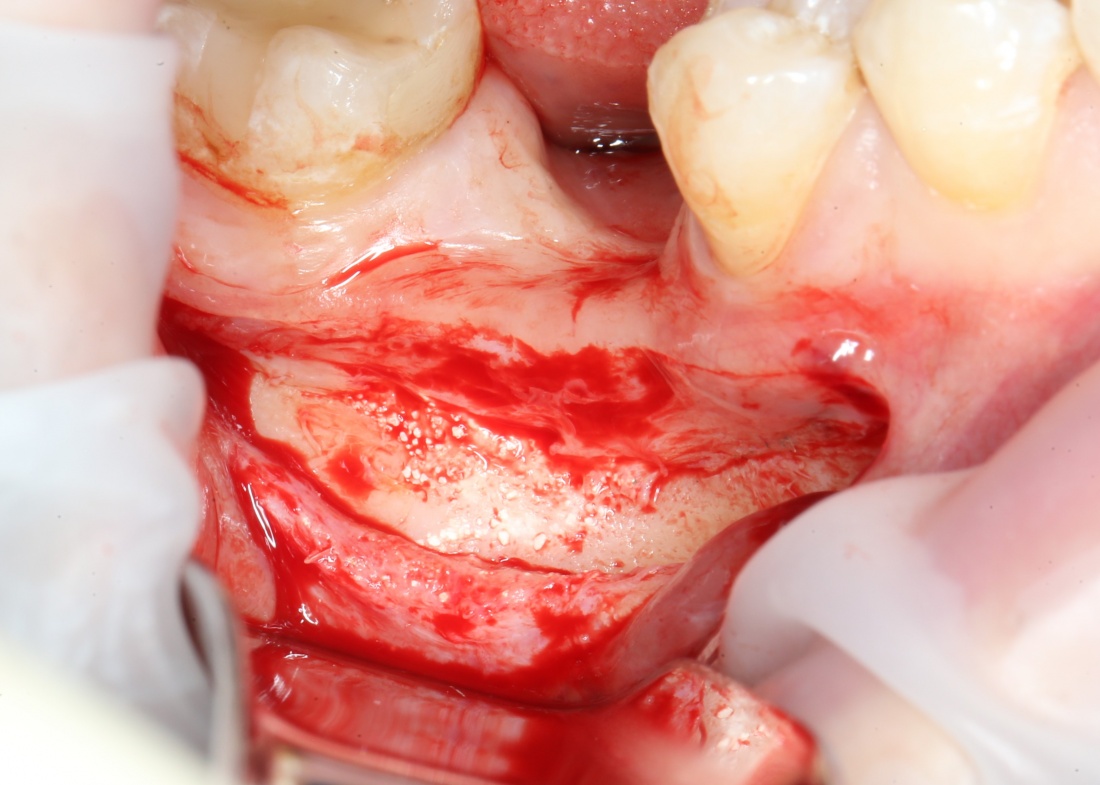

Для получения костного блока, мы открываем донорскую зону, наружную косую линию нижней челюсти.

Подготовка костного ложа и фиксация аутотрансплантата

Возвращаемся к основной операционной области. Еще раз посмотрим на альвеолярный гребень, поофигеваем от его ширины и моих грандиозных планов:

Если ты читал мои предыдущие публикации, посвященные остеопластике, то наверняка знаешь, что костное ложе перед фиксацией графта (любого графта) требует некоторой подготовки. В основном она заключается в полном или частичном удалении кортикального слоя и, применительно к АТККФ — адаптации не только блока под ложе, но и ложа под пересаживаемый костный блок. Подробности здесь>>

Я зафиксировал костный блок практически без адаптации на несколько винтов. Обрати внимание, что винты находятся в зоне, где не планируется установка имплантатов. Фиксация должна быть надежной, поскольку мне еще предстояла подготовка лунок для имплантатов. Трех винтов для этого вполне достаточно.